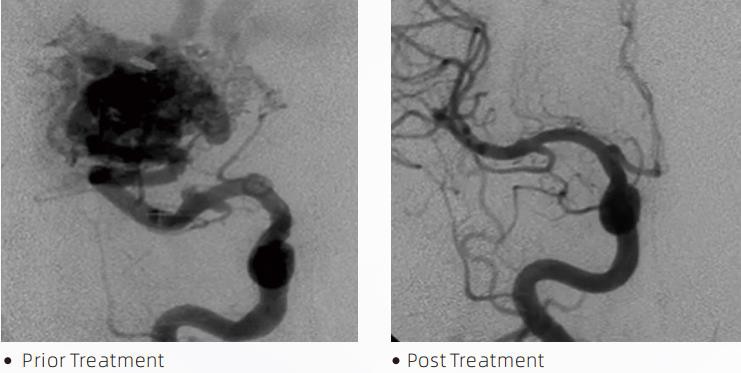

LavaTMLiquid Embolic System adalah terapi endovaskular intervensi untuk pengobatan malformasi serebrovaskular. Malformasi serebrovaskular mengacu pada sekelompok kelainan neurovaskular jinak atau ganas yang dapat menyebabkan perdarahan intrakranial, infark serebral, iskemia serebral, dan penyakit lainnya. Sistem embolisasi cair adalah perangkat medis yang diberikan melalui penyisipan intravaskular sederhana, yang mengembolisasi pembuluh darah otak abnormal dengan menyuntikkan bahan cairan khusus. Bahan cairan tersebut membentuk emboli jaringan terkontrol di dalam pembuluh darah, sehingga dapat mengurangi dampak malformasi serebrovaskular pada pasien. Kateter mikro pengiriman yang kompatibel dengan DMSO yang diindikasikan untuk digunakan dalam neurovaskular digunakan untuk mengakses situs embolisasi. Agen emboli cair lava adalah sistem agen emboli cair non-perekat yang terdiri dari kopolimer EVOH (etilen vinil alkohol) yang dilarutkan dalam DMSO (dimetil sulfoksida), dan bubuk tantalum mikron tersuspensi untuk memberikan kontras untuk visualisasi di bawah fluoroskopi. LaharTMtersedia dalam tiga formulasi produk, LAVA-12, LAVA-18 dan LAVA-34. LAVA-12: Direkomendasikan saat memberi makan pembuluh mikro distal dan melalui pengumpan kecil. LAVA-18: Direkomendasikan saat pemberian suntikan pedikel akan dilakukan dekat dengan nidus; LAVA-34: Direkomendasikan untuk embolisasi komponen aliran tinggi dan lebih besar.